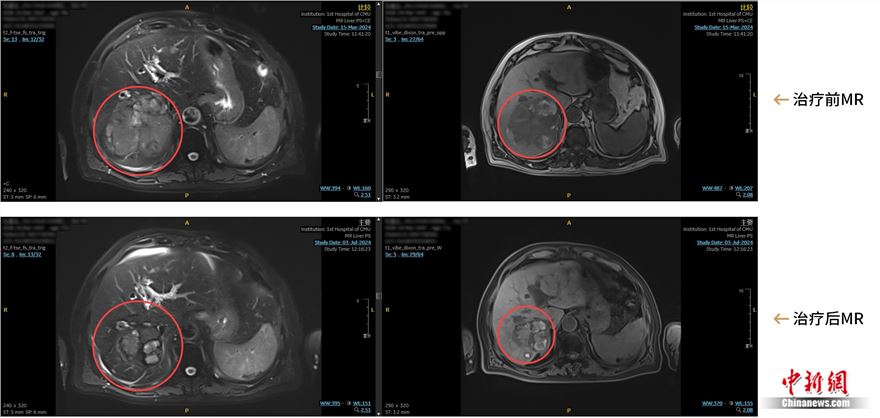

钇90治疗,术前和术后三个月MR对比影像

患者是一位77岁的老人。手术3个半月后,最近一次复查结果显示,老人的肿瘤已经小了将近一半。随着时间的推移,体内肿瘤或许还将逐渐缩小,直至最终消失。